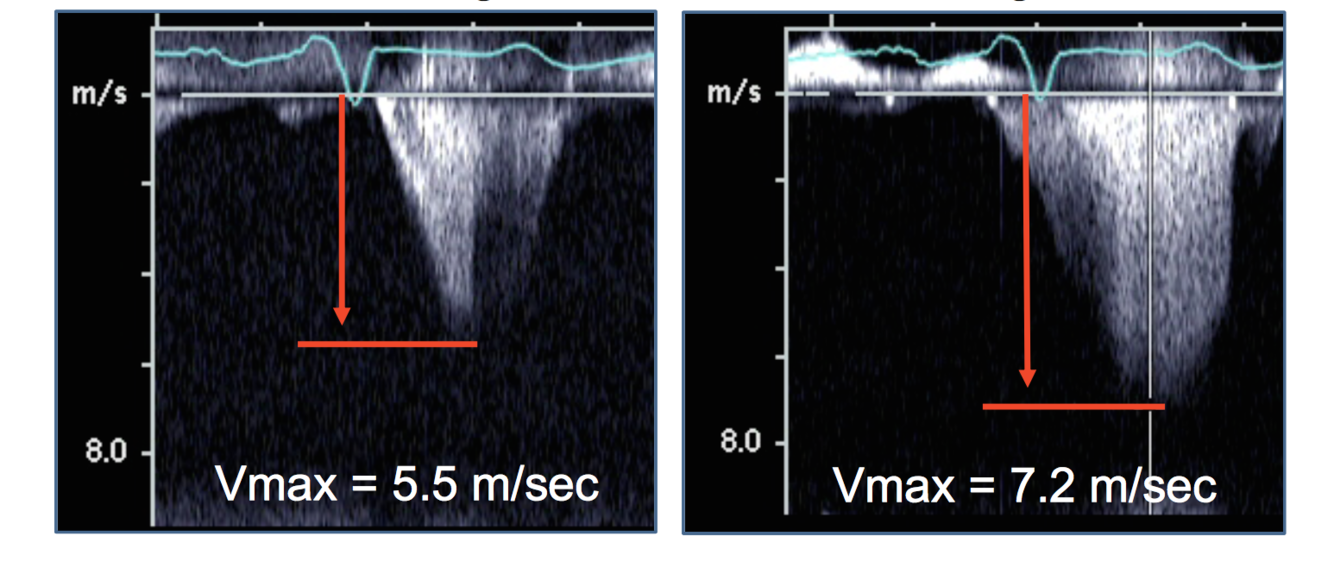

diagnose each doppler signal